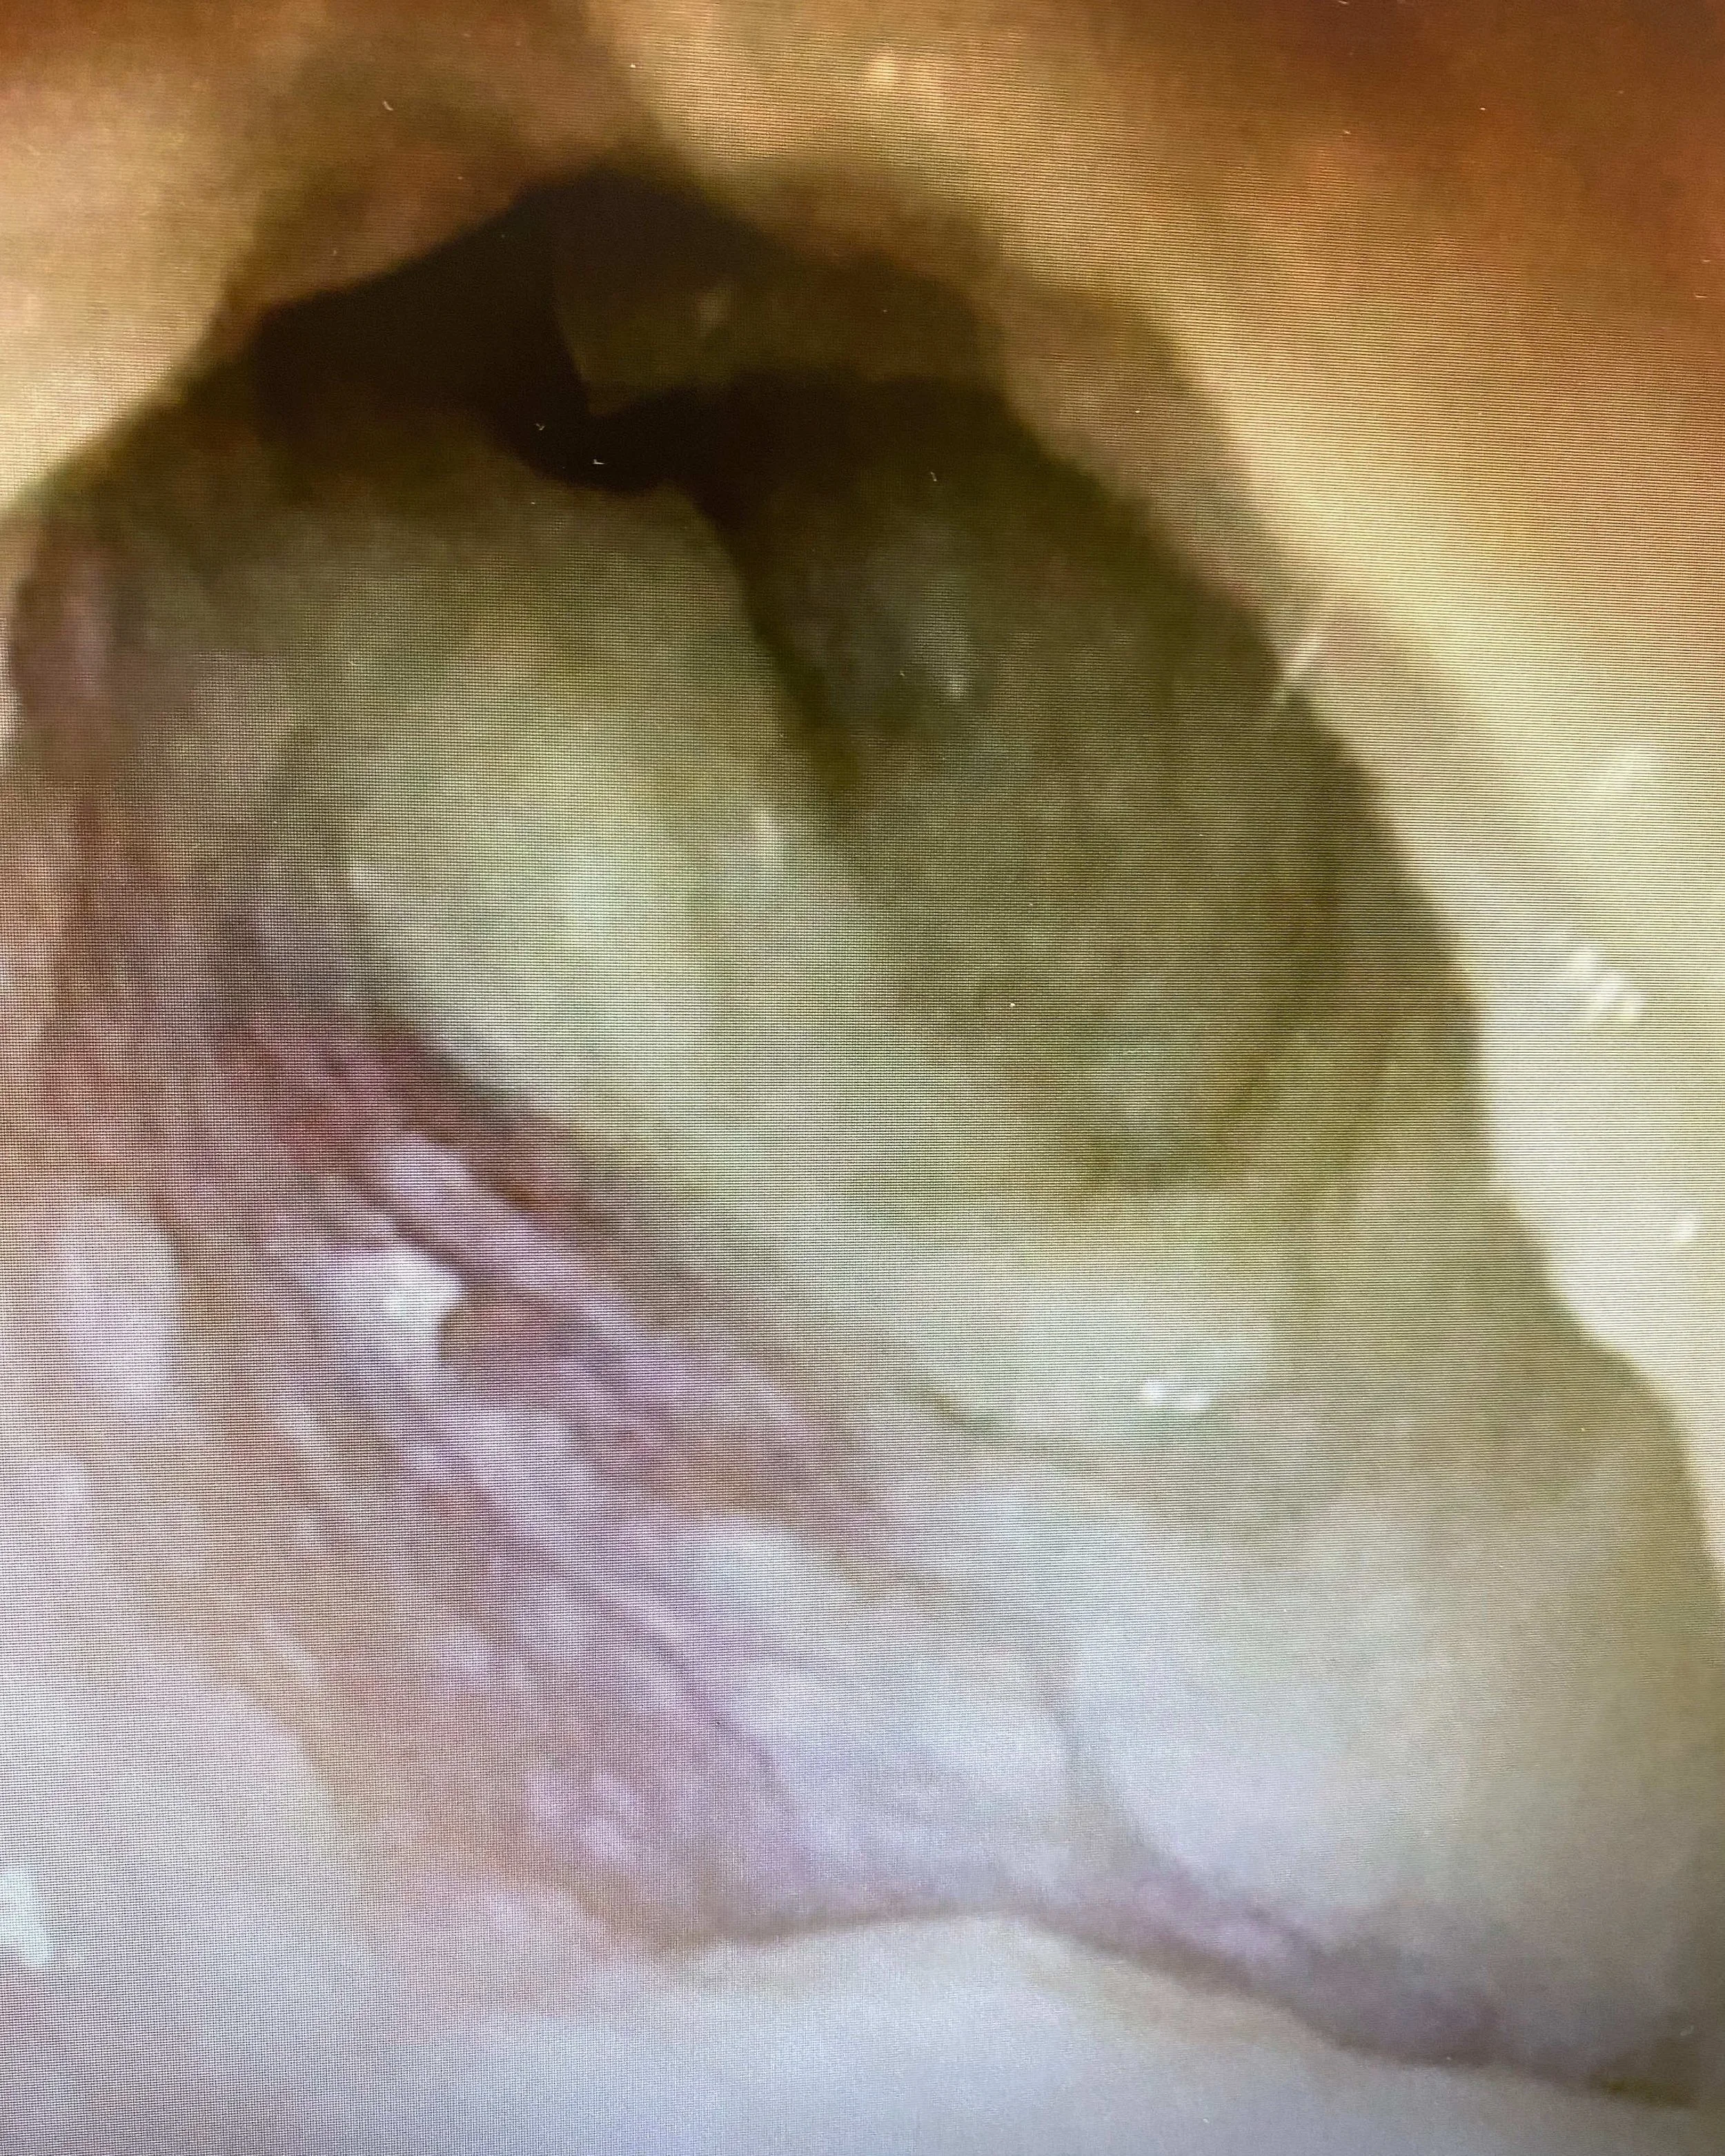

“Here is a good old-fashioned acute otitis externa. Is it fungus? Is it bacteria? Both? You’ll never know until they fail treatment and weeks have gone by.”

Matthew Branch, M.D.

CEO and Co-founder, ENTRx

BEFORE TREATMENT